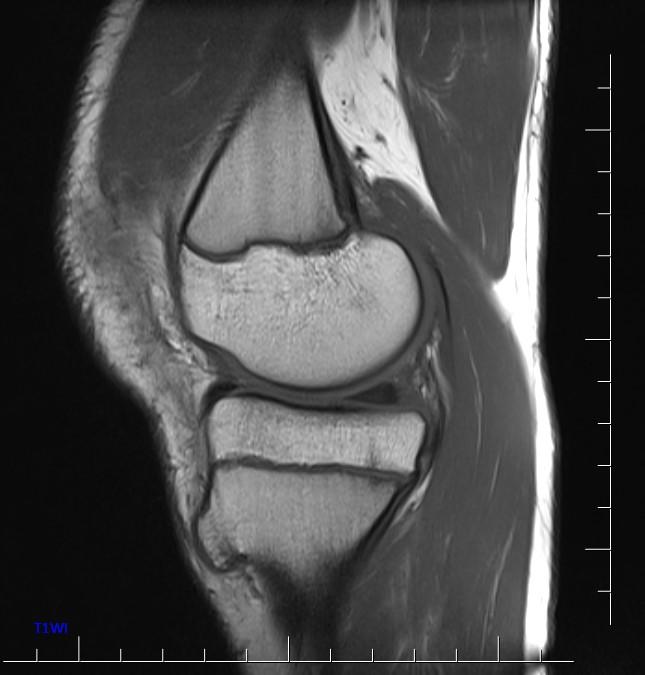

*13-year-old boy with mass on the proximal tibia.

Answer: Osteochondroma

MR images show osteochondroma on the proximal tibia.

MRI is the best imaging procedure to evaluate cartilage thickness, presence of edema in bone or adjacent soft tissues, and visualizing neurovascular structures in the vicinity.

The cartilage cap appears the same as cartilage elsewhere, with intermediate to low signal on T1WI and high signal on T2WI. The cartilage cap of over 1.5 cm in thickness is suspicious for malignant degeneration. The cartilaginous cap itself should not enhance.